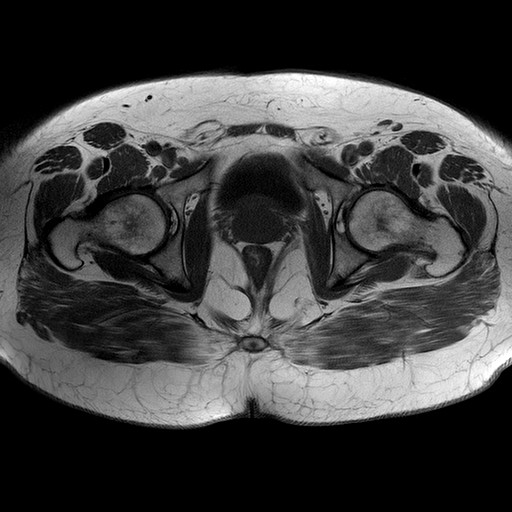

Esami: RMN BACINO

Evidenti e simmetriche alterazioni osteofitosiche in regione coxo femorale con riduzione delle rime articolari. Degenerazione completa del cercine glenoideo. Non attuali segni di versamento articolare. Non segni di edema osseo che escludono attuale algodistrofia od osteonecrosi. Lieve e simmetrica riduzione del trofismo della muscolatura glutea.